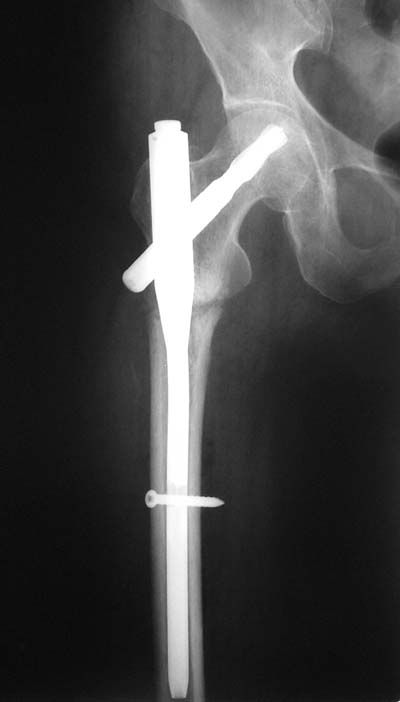

Да? Качество рентгенограмм конечно неочень, но ведь это нестабильный перелом 31.А2.2, не так ли?

Не думаю так. см вложение.

> Да? Качество рентгенограмм конечно неочень, но ведь это

> нестабильный перелом 31.А2.2, не так ли?

Ну, после помещения туда такого гвоздя даже без дистального винта заметной нестабильности уже не остается ;-)

> Не думаю так. см вложение.

Для такого перелома вполне может быть использован диафизарный штифт, который отечественного производства я даже боюсь считать во сколько раз дешевле... Недавно несколько примеров я закидывал.